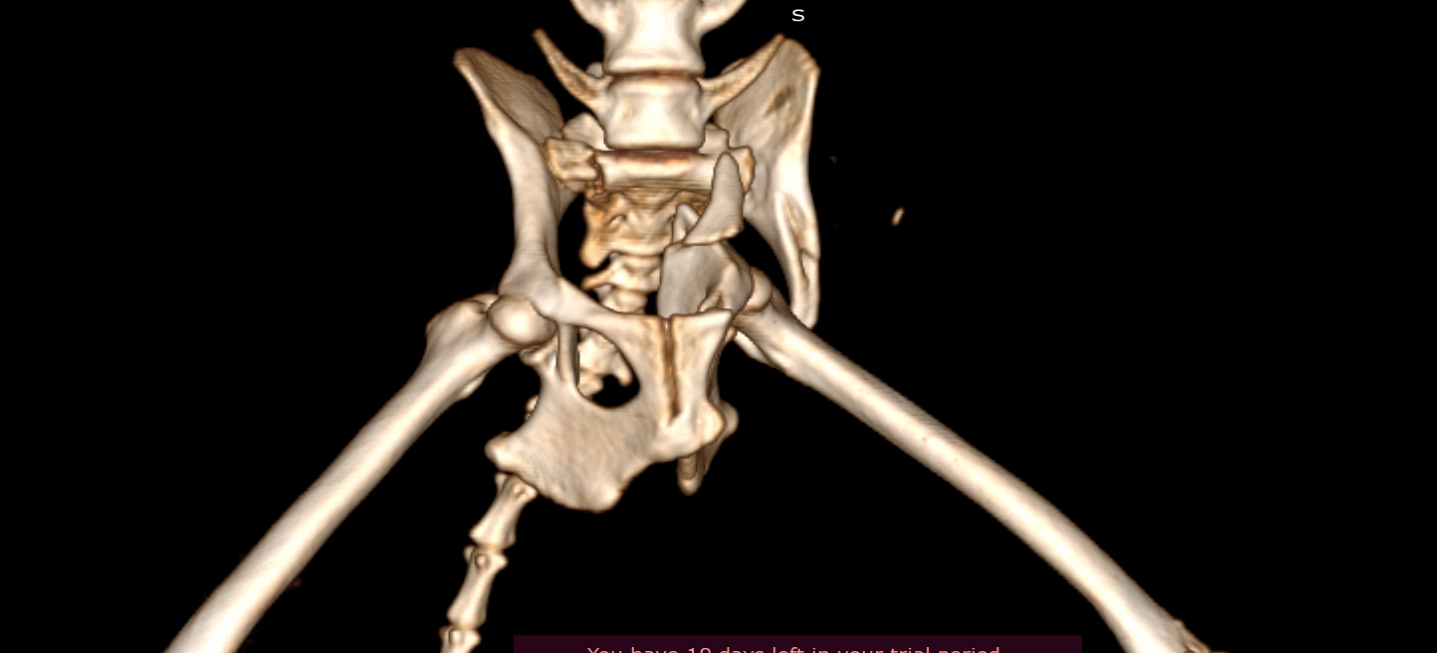

狗狗 車禍 骨盆骨折

狗狗的骨盆骨折相對於常見的四肢骨折 不容易單純靠xray 診斷及擬定手術計畫藉由電腦斷層影像的支援 能提高手術成功的機率

14kg 11歲的莓莓 術後10個月追蹤 行動自如一切正常喔

電腦斷層影像